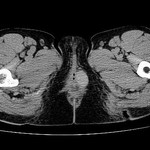

[画像診断]虫垂の粘液嚢腫(mucocele)について 2010-10-14